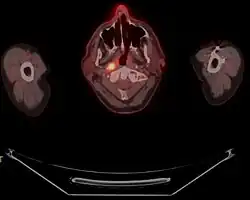

-

Stage T1 nasopharyngeal cancer

Stage T2 nasopharyngeal cancer

Stage T3 nasopharyngeal cancer

Stage T4 nasopharyngeal cancer